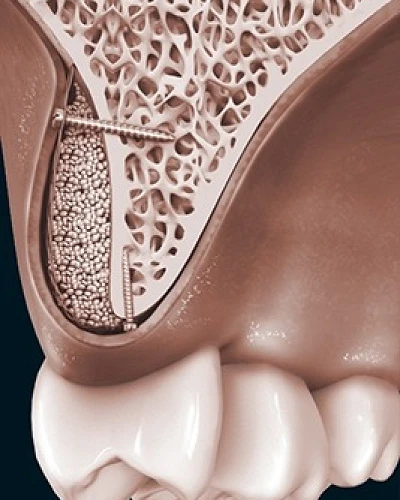

Elevación de Seno Maxilar

Consiga una base sólida para sus implantes dentales con nuestra cirugía especializada de Elevación de Seno. Cuando el maxilar superior carece de altura ósea suficiente, realizamos una elevación precisa de la membrana sinusal. Mediante la colocación cuidadosa de material de injerto óseo de alta calidad, regeneramos el volumen necesario, garantizando la estabilidad y el éxito a largo plazo de sus futuros implantes en la zona de los molares.